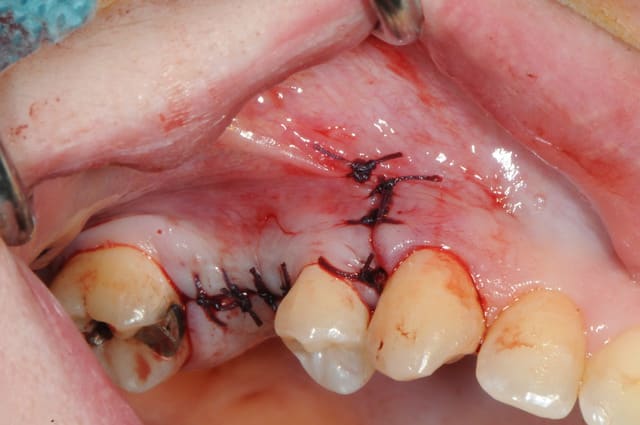

le sujet tombe à pic!

je viens de faire un sinus lift ce matin;

- 3 à 4 mm de hauteur sous sinusienne

- des cloisons de refend partout

- comblement avec du Vital Os

- un implant Axiom D4 L 10

comme je n'avais pas le temps de faire des photos la dernière fois et que j'en étais frustré, je me suis un peu lâcher aujourd'hui...

les premières photos, c'était ouverture par voie latérale

- sutures...